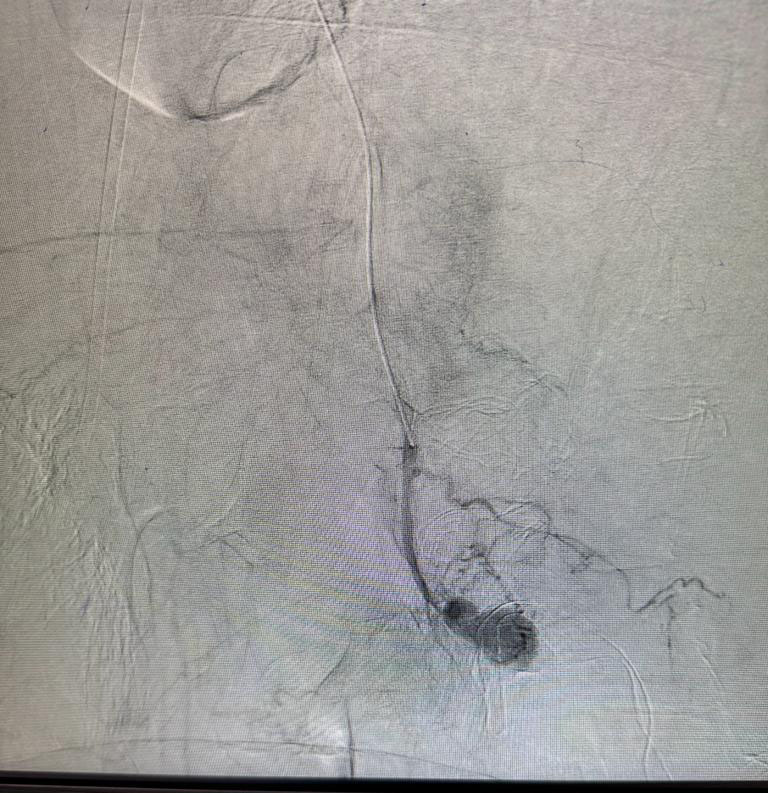

Gross hemoptysis in known case of pulmonary tuberculosis, bronchial artery embolization done